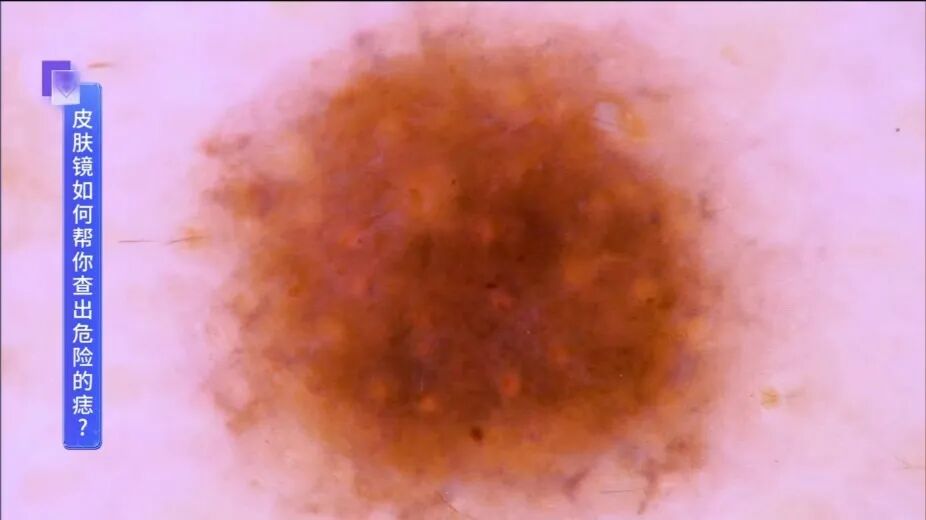

良性的色素痣,多为规则的色素分布↓